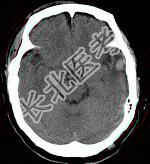

- 单项选择题成年男性,外伤后一小时, CT检查如图,最可能的诊断是 ( )

A、脑挫裂伤

B、脑转移瘤

C、钙化灶

D、脑膜瘤

E、脑出血